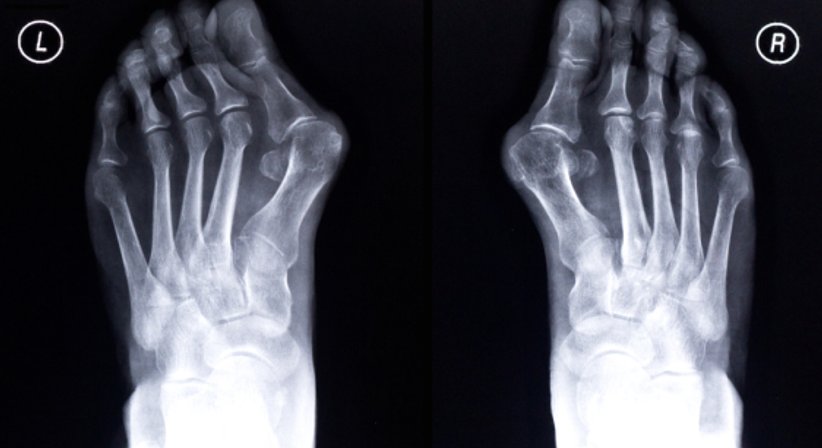

Der Hallux valgus ist die am häufigsten auftretende Zehenfehlstellung. Die Fehlstellung ist durch eine Deformierung des Großzehenballens charakterisiert; die Großzehe weicht von ihrer natürlichen Position ab und beginnt sich in Richtung der anderen Zehen abzuwinkeln. Häufig "verdrängt" die Großzehe die anderen Zehen sogar von ihrer natürlichen Stellung. In Folge der Schiefstellung wölbt sich der Ballenbereich am Innenfuß nach vorne.

Typisch für einen Hallux valgus ist das sichtbar hervortretende Köpfchen an der Innenseite vom Fuß. Mit fortschreitendem Verlauf kommt es zu Schmerzen, insbesondere dann, wenn der vergrößerte Ballen beim Gehen gegen die Schuhe drückt. Durch das Tragen zu enger Schuhe kommt es zu einer dauerhaften Reizung der Haut und des darunterliegenden Gewebes und in weiterer Folge zu Schwellungen und Entzündungen.